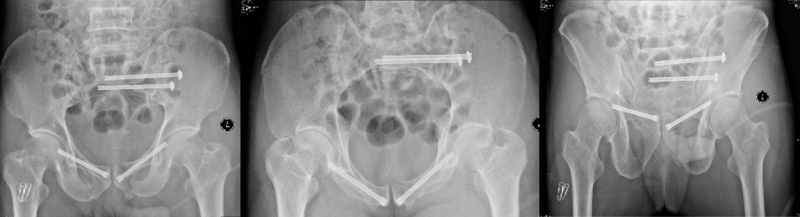

術(shù)前X線片

手術(shù)中

術(shù)后X線片